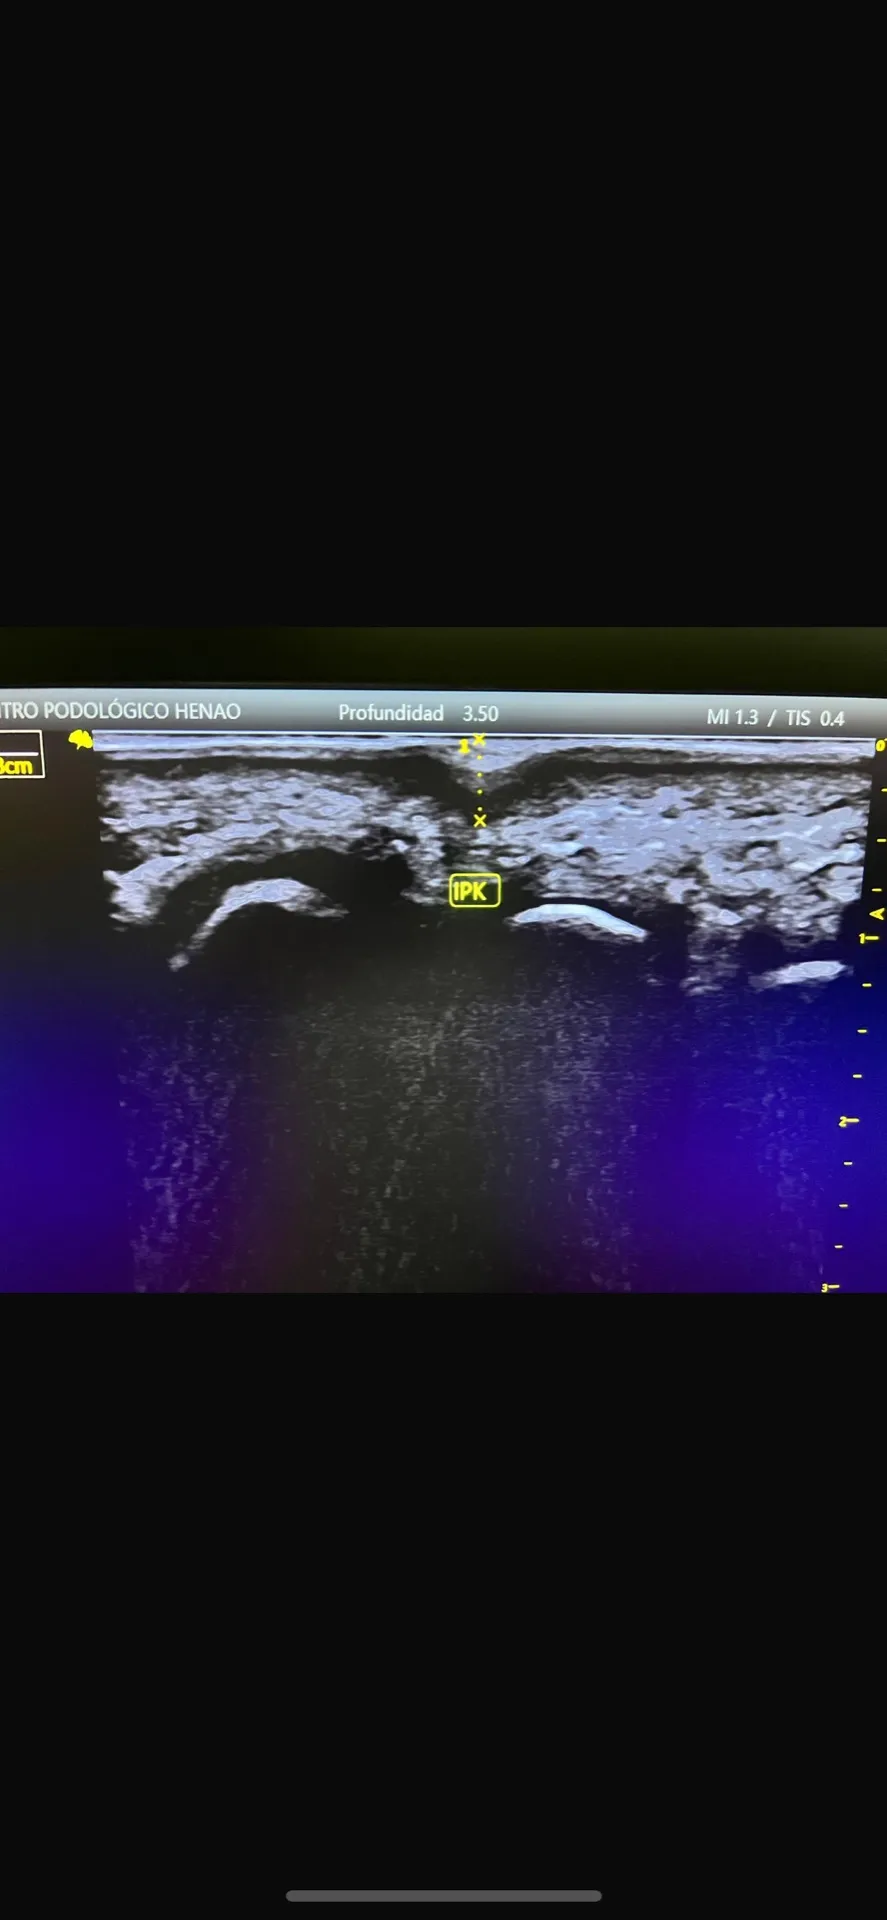

Utilizamos plataforma de presiones computarizada, análisis de la marcha, evaluación del rango de movimiento articular, y cuando es necesario, ecografía musculoesquelética para comprender exactamente qué está causando la hiperpresión.

Figura 6: El estudio ecográfico nos permite ver estructuras que no son visibles a simple vista y planificar el tratamiento con precisión.